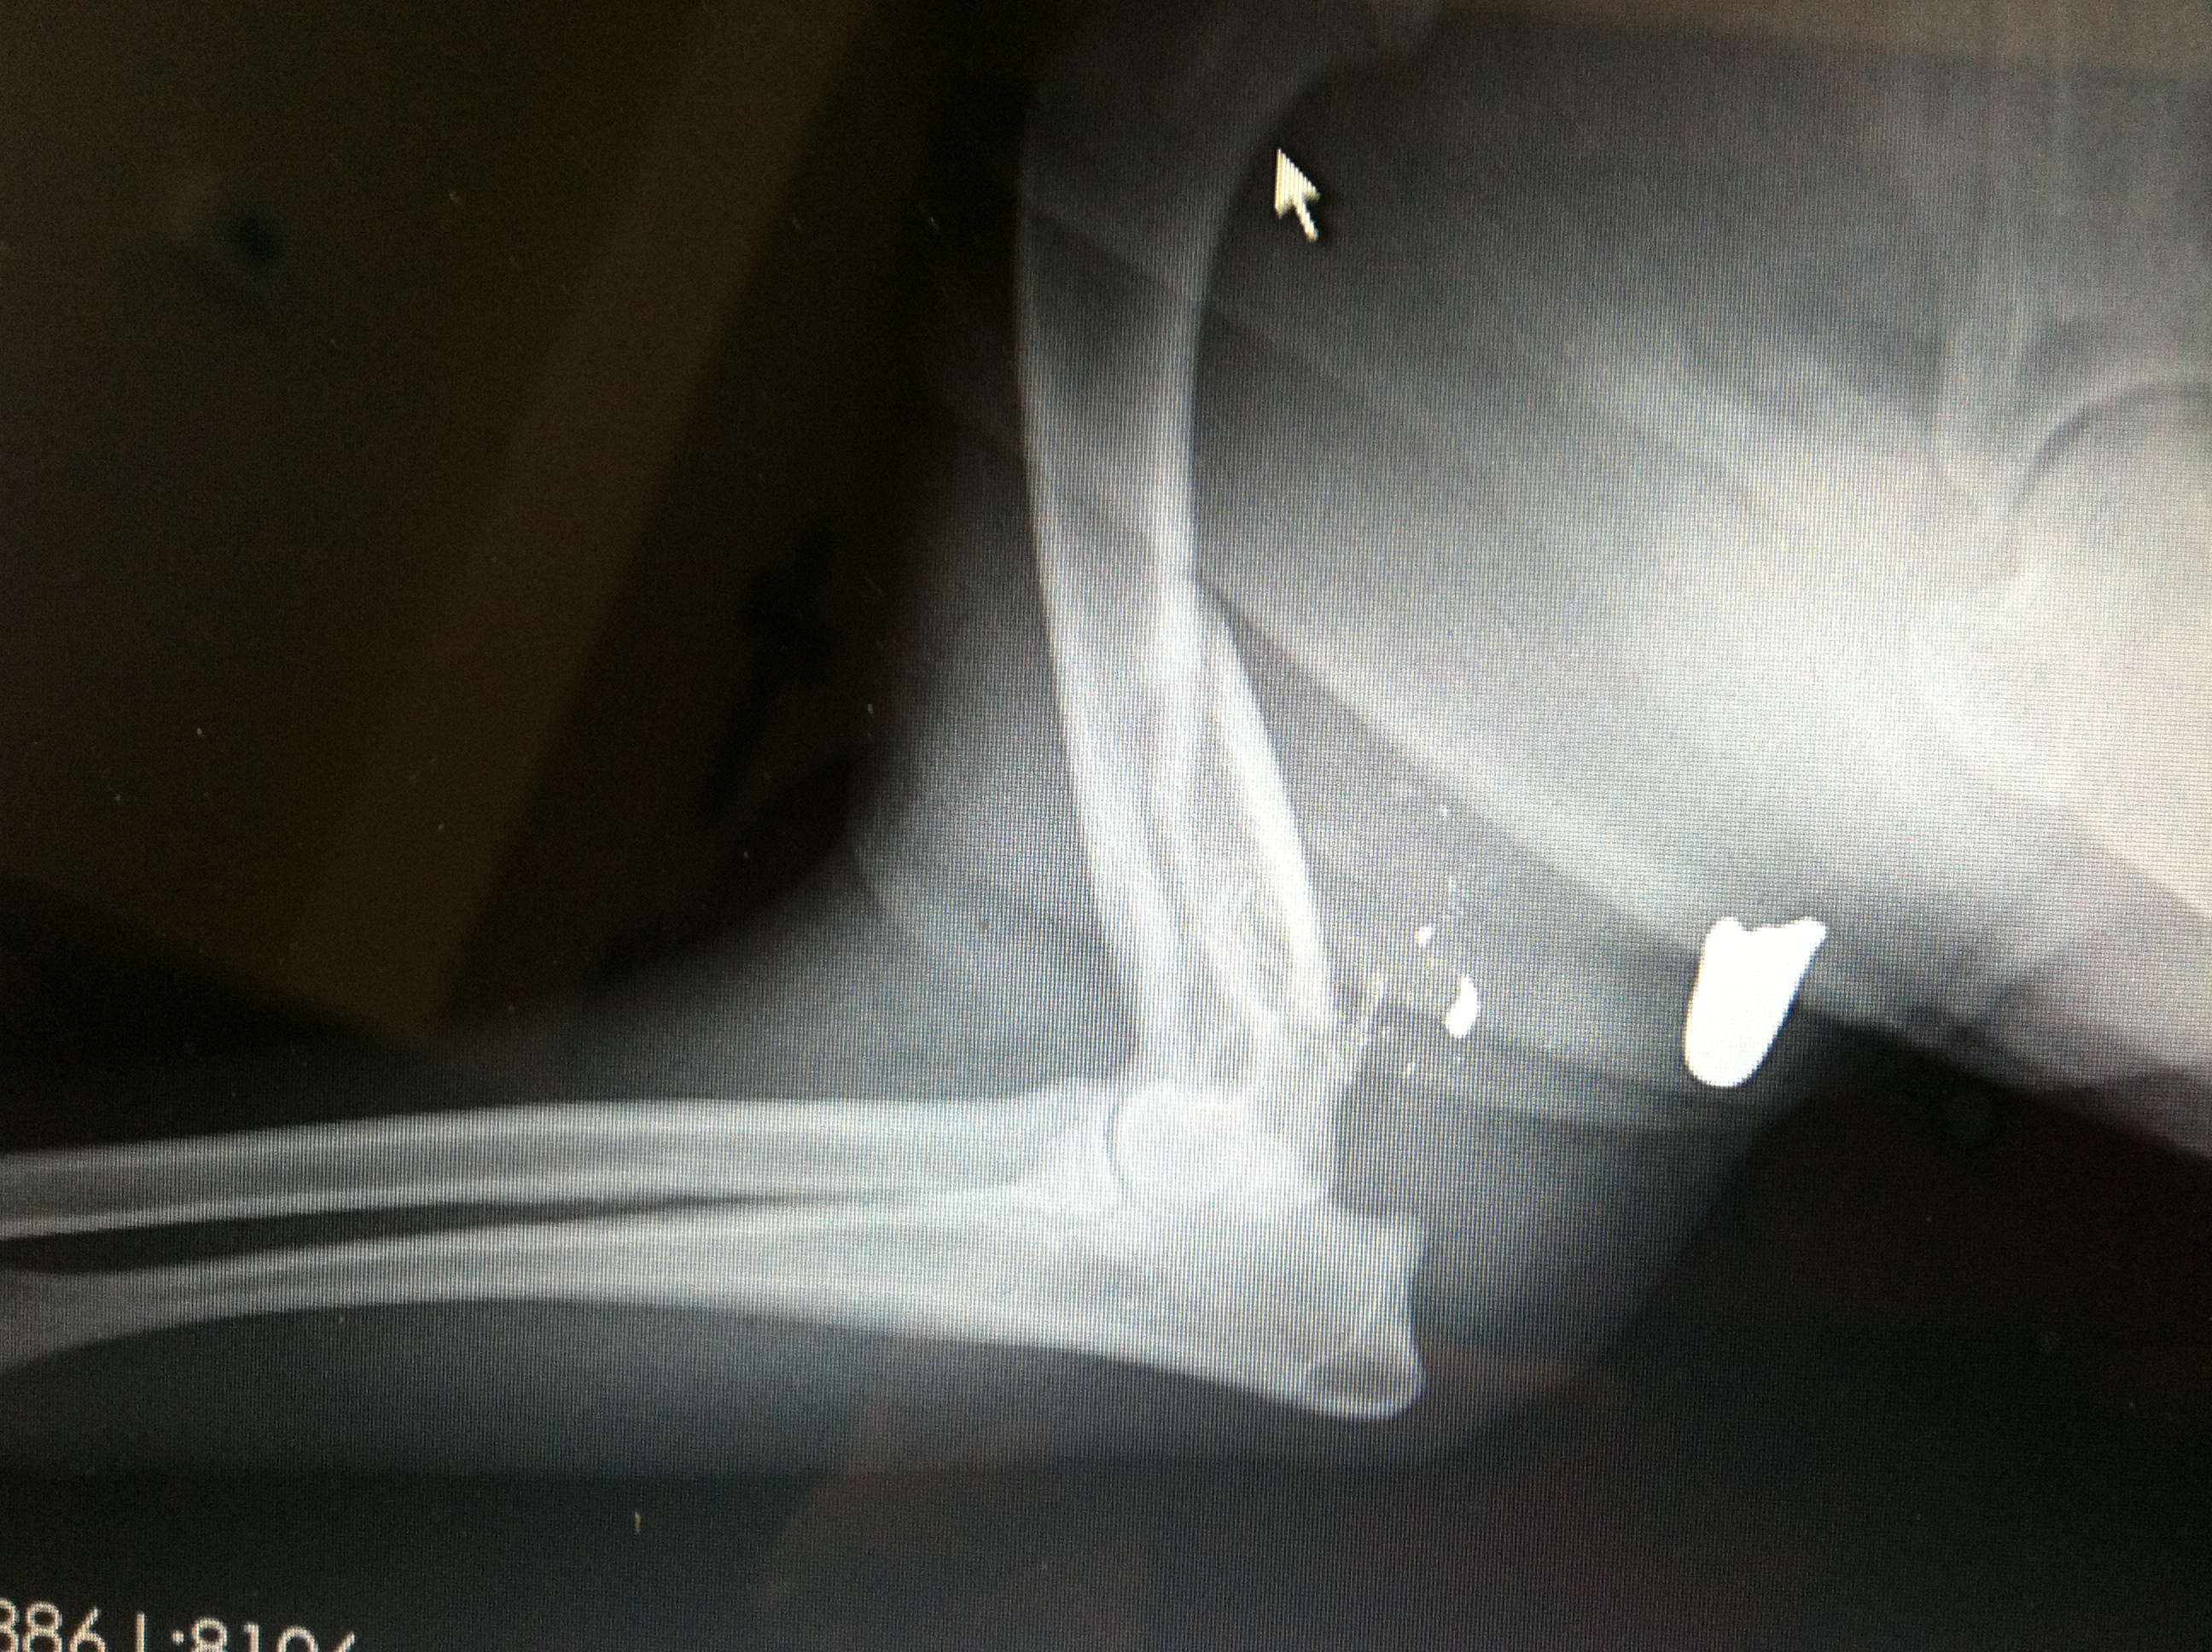

Wesson was transferred to the caring volunteers at Mended Hearts Rescue and taken to a local veterinarian for evaluation of an injury to his right front leg. The x-rays of his leg showed a severe fracture of the humerus (upper arm bone) and a bullet lodged within the surrounding muscle.

I love my friends, and I also love my new iphone. (See, I told you it’d seem random, just hang in there) Within moments I was able to text a picture of the x-rays to three of my orthopedic surgeon friends and, within moments, I got three definitive opinions in favor of limb amputation. (Props to Dr. Amy Fauber, Dr. Todd Reicks, and Dr. Aaron Wehrenberg for their fast, free orthopedic consults!)

The location of the trauma meant permanent nerve damage for poor Wesson. This would mean chronic pain and lameness if left alone. Once the verdict was in, Wesson was immediately scheduled for surgery.